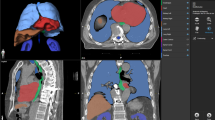

Segmentation and landmarking of computed tomographic (CT) images of pediatric patients are important and useful in computer-aided diagnosis, treatment planning, and objective analysis of normal as well as pathological regions. Identification and segmentation of organs and tissues in the presence of tumors is difficult. Automatic segmentation of the primary tumor mass in neuroblastoma could facilitate reproducible and objective analysis of the tumor’s tissue composition, shape, and volume. However, due to the heterogeneous tissue composition of the neuroblastic tumor, ranging from low-attenuation necrosis to high-attenuation calcification, segmentation of the tumor mass is a challenging problem. In this context, we explore methods for identification and segmentation of several abdominal and thoracic landmarks to assist in the segmentation of neuroblastic tumors in pediatric CT images.

Methods are proposed to identify and segment automatically peripheral artifacts and tissues, the rib structure, the vertebral column, the spinal canal, the diaphragm, and the pelvic surface. The results of segmentation of the vertebral column, the spinal canal, the diaphragm and the pelvic girdle are quantitatively evaluated by comparing with the results of independent manual segmentation performed by a radiologist.

The use of the landmarks and removal of several tissues and organs assisted in limiting the scope of the tumor segmentation process to the abdomen, and resulted in the reduction of the false-positive error rates by 22.4%, on the average, over ten CT exams of four patients, and improved the result of segmentation of neuroblastic tumors.